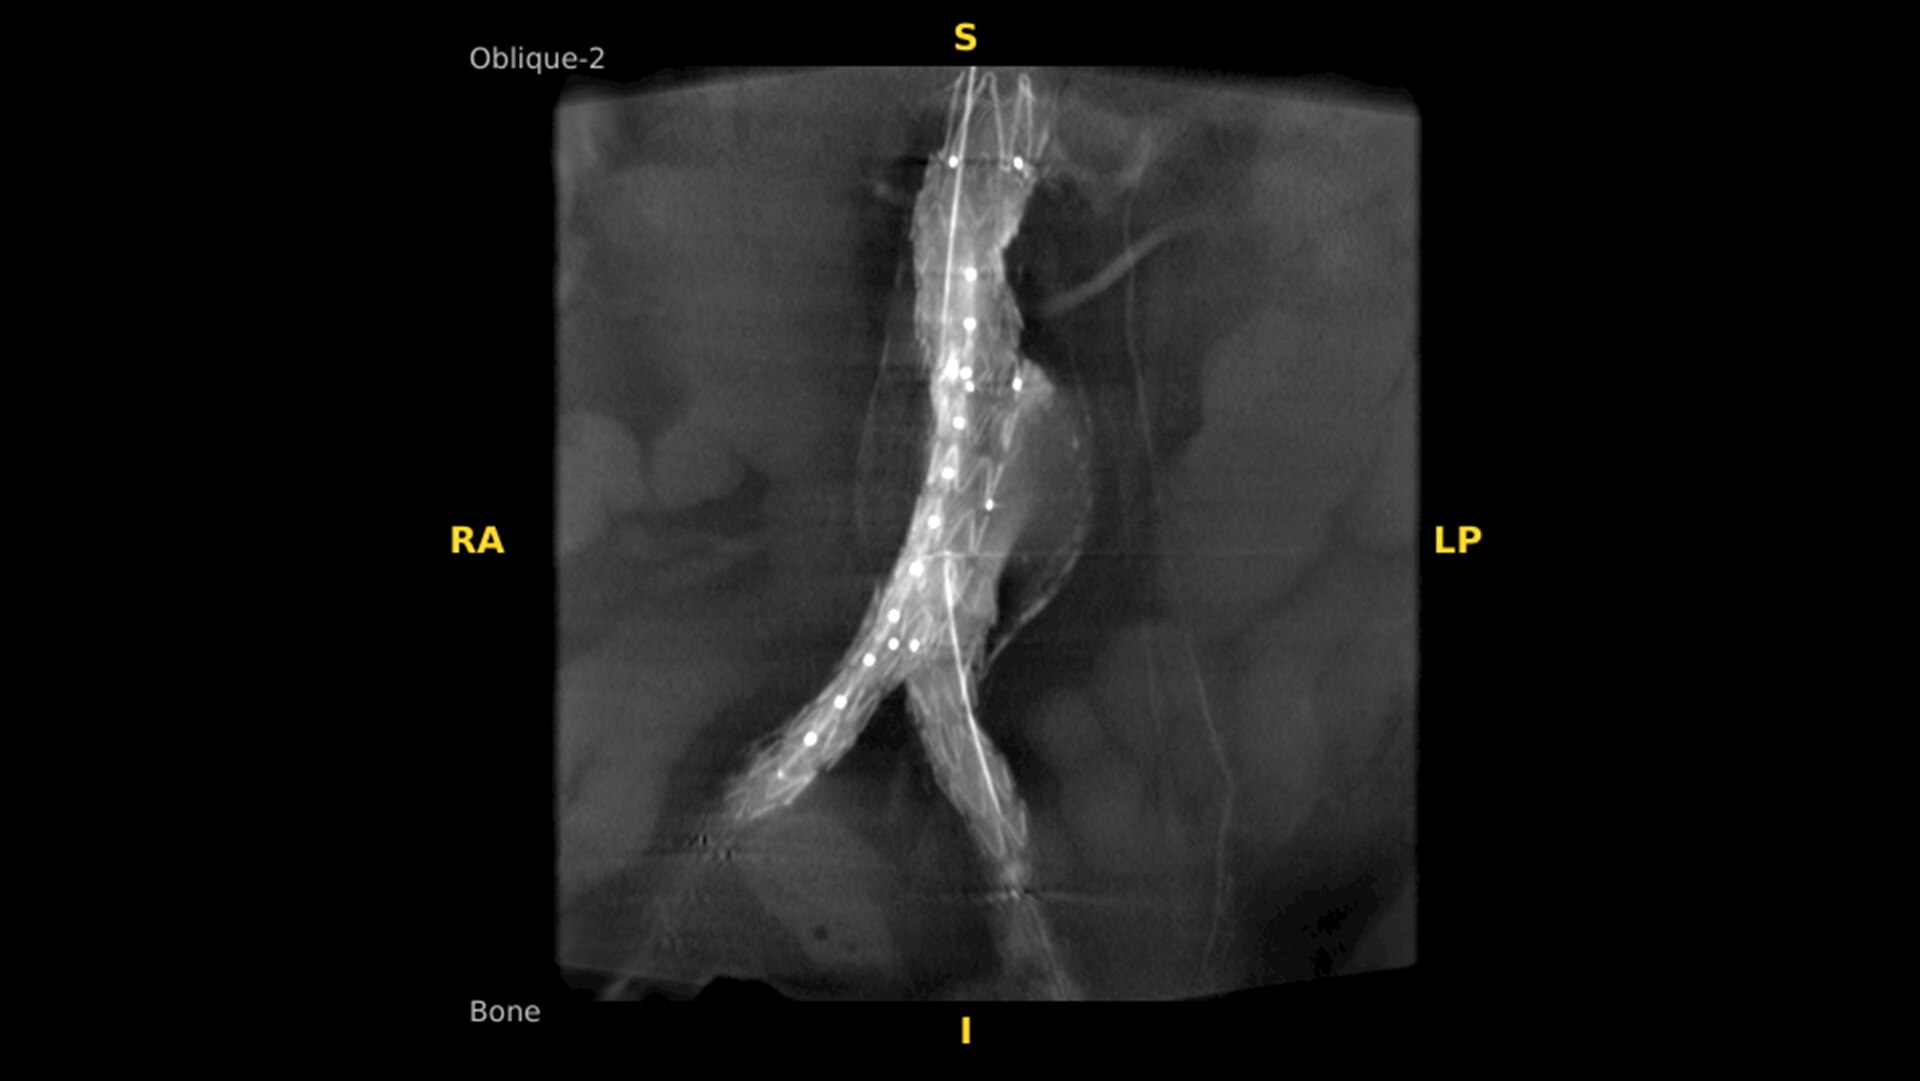

19 cm3 CT-like images presented intraoperatively in minutes

See more levels during a spinal fusion, or more of the pelvis or femur during an orthopedic procedure. With a 19 cm x 19 cm x 19 cm volume, OEC 3D captures a 67% greater volume than other 3D C-arms*.

Enhance intraoperative decision-making with visualization capabilities of Augmented Fluoroscopy in the OEC 3D Volume Viewer. Analyze five perspectives with 3D imaging tools including Multi-Oblique Mode, scrolling 512 slices, zoom, and more.